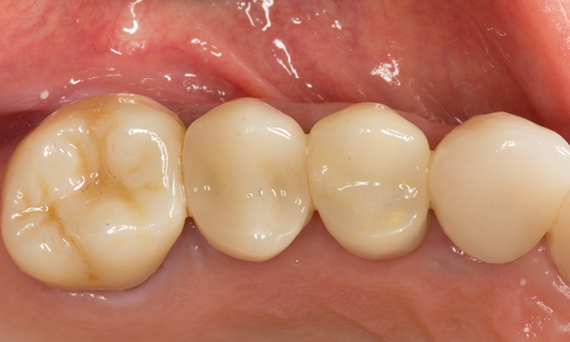

Quadrant rehabilitation

Two CEREC Tessera crowns and two inlays

Within a single visit of four hours the restoration of two crowns and two inlays, which were 15 years old, was carried out. The patient was very pleased with the very good aesthetic result.

Before: Insufficient fillings in the second quadrant. The restorations were about 15 years old.

After: Chairside-fabricated crowns made from CEREC Tessera (teeth 26/27). Inlays for teeth 24 and 25 made of composite blocks.